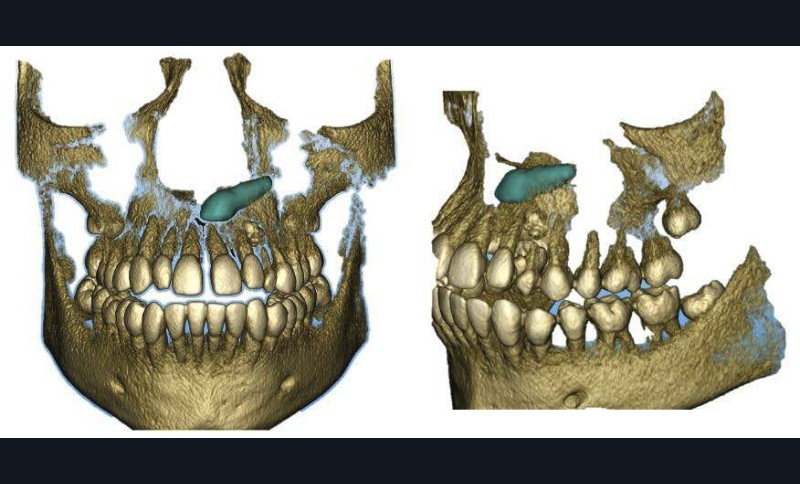

La radiographie panoramique permet de confirmer l’inclusion de la 23, apicale aux dents 21 et 22, ainsi que la présence d’un odontome en apical de la 63. Ces éléments nécessitent la réalisation d’un CBCT.

Le CBCT révèle une position très apicale de la 23. L’apex est fermé.

- mise en place de la 23 sur l’arcade par auto-transplantation étant donné la position très défavorable de la dent, associée à l’extraction de la 63 et de l’odontome ;